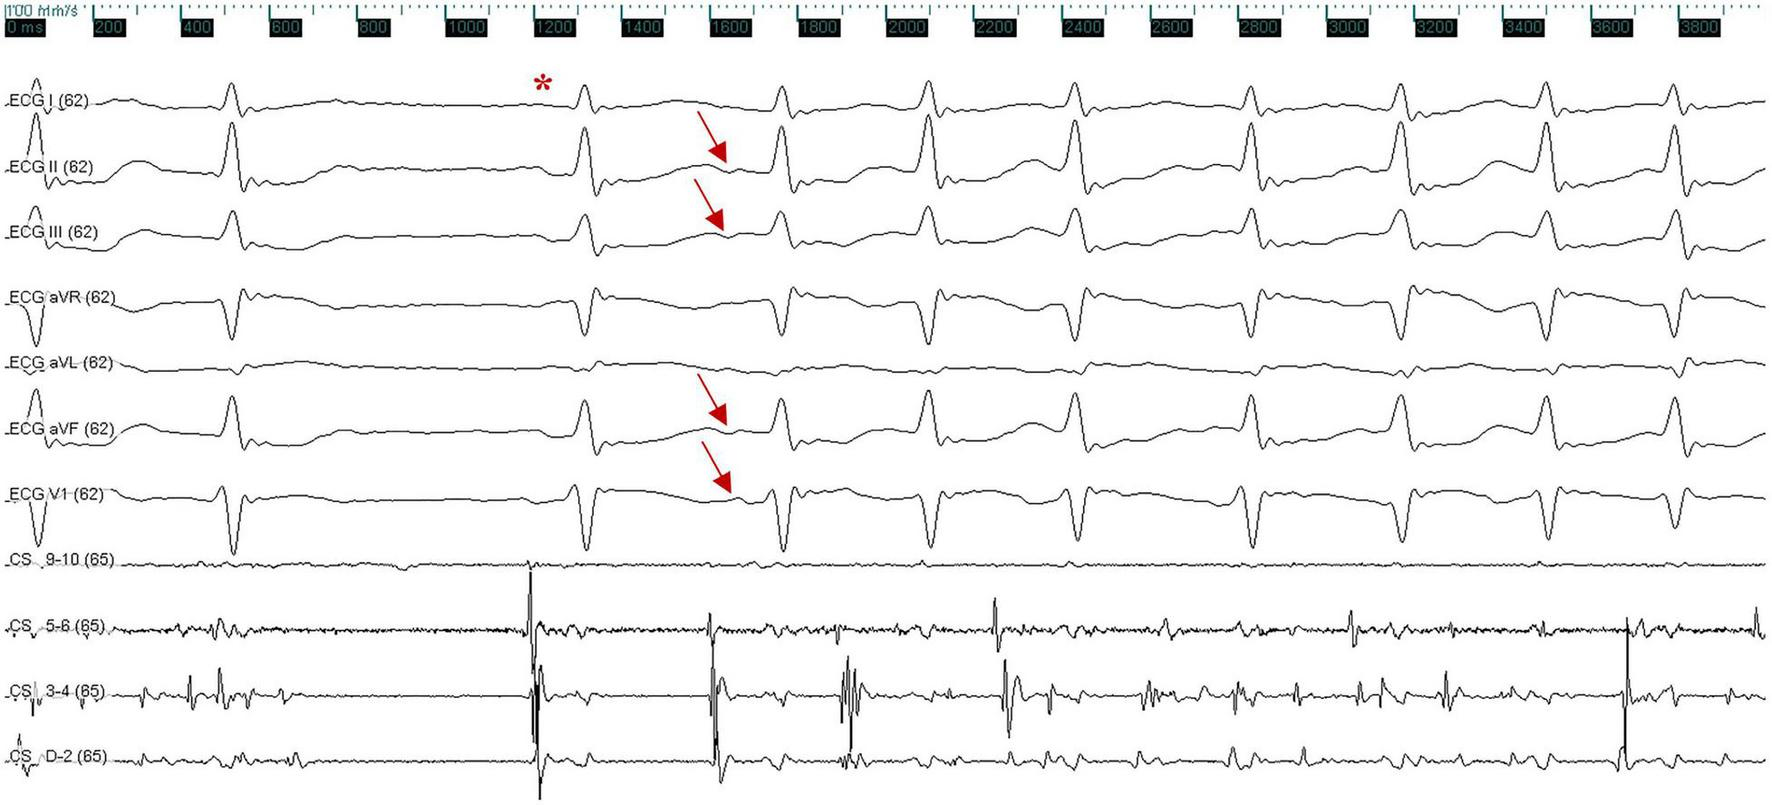

FIGURE 2

Surface and intracardiac electrocardiogram indicate the termination of atrial fibrillation, followed by a sinus beat (red asterisk); atrial fibrillation was triggered again by a premature atrial complex, which exhibited a negative P wave in inferior leads (II, III, and aVF) and a positive P wave in lead V1 (red arrow). The ECG was recorded at a speed of 100 mm/s. X axis, time line; y axis: gain. CS, coronary sinus; ECG, electrocardiogram.